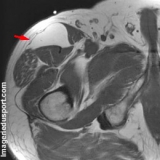

IRM :

- En T1, hypersignal

- En T2, signal intermédiaire (effacement sur séquence avec suppression de graisse)

- après injection de Gadolinium

* pas de rehaussement

-  limites nettes, avec souvent septations internes.